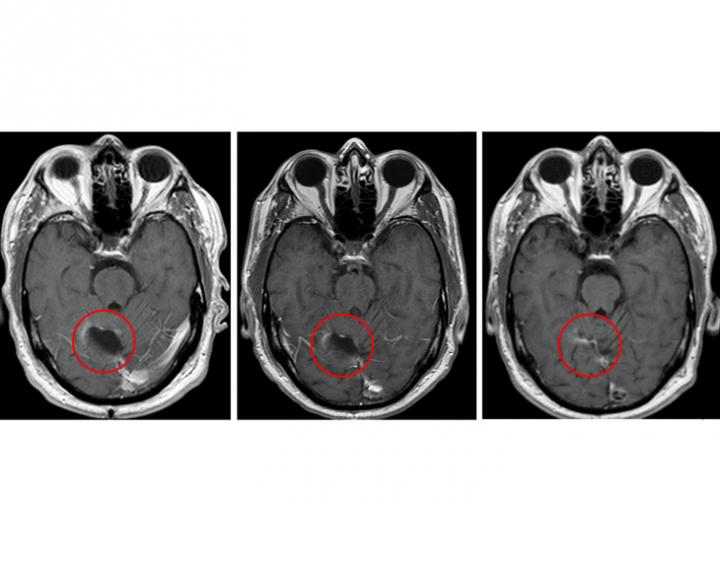

Although the trial was small and not designed to evaluate efficacy, four of the 11 study patients survived for more than five years following treatment with a combination of vaccine and the drug temozolomide, a first-line chemotherapy drug for glioblastoma. That outcome is uncommon for glioblastoma, a lethal brain cancer that has a median survival of nearly 15 months when treated with the current standard of care.

Batich said the approach significantly slowed the progression of patients' tumors. Typically, glioblastoma tumors begin to regrow after standard treatment at a median of eight months, but for study participants, recurrence occurred at a median of 25 months.